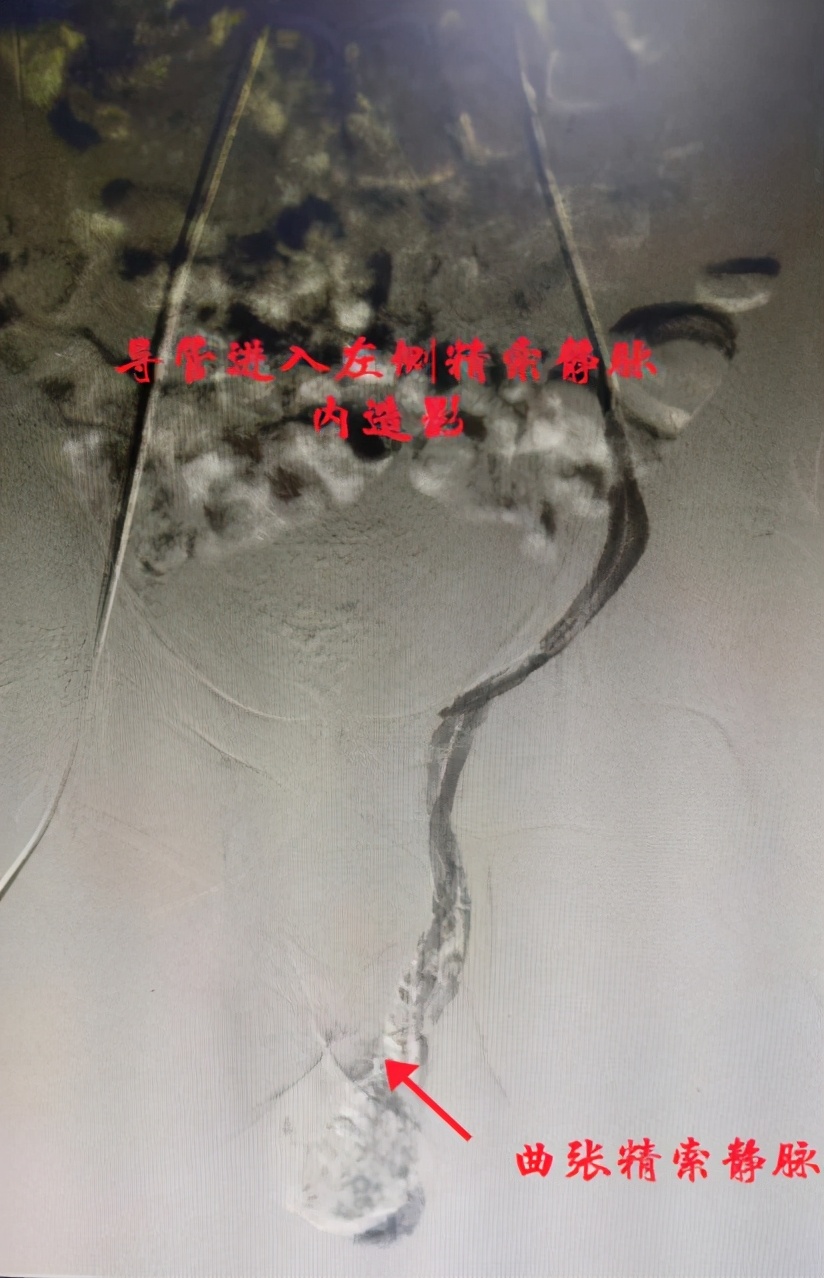

这天小张一大早便找到了自治区南溪山医院血管外科副主任胡长付,在胡主任的耐心解说下小张忐忑的内心终于平静下来。“我们将使用小小的穿刺针穿刺股静脉,送入导管至精索静脉内,”胡长付主任说道:“使用一种药物注入栓塞,便可治疗曲张精索静脉,手术后只留一针尖大小穿刺点,不留疤痕。”

据胡长付主任介绍,其实精索静脉曲张是一种血管病变,指精索内蔓状静脉丛的异常扩张、伸长和迂曲,可导致疼痛不适及进行性*丸睾**功能减退,是男性不育的常见原因之一。通常见于左侧,约占77%-92%,双侧为7%-22%,单纯发生于右侧的少见,为1%。精索静脉曲张在普通男性人群中患病率为10%-15%,在原发性男性不育中占到30%-40%,在继发性不育中为69%-81%。

同时胡长付主任也呼吁有精索静脉曲张的病人不要讳疾忌医,精索静脉曲张的外科治疗仍是目前最常见的男性不育外科治疗手段之一,精索静脉曲张的外科治疗方式包括手术治疗和介入治疗(顺行或逆行)。介入下精索静脉栓塞手术具有创伤小、恢复快、费用低、住院时间短特点。对该疾病的治疗有立竿见影的效果。希望广大患者在尚未造成严重后果前,前往三甲医院就诊,以免延误病情。